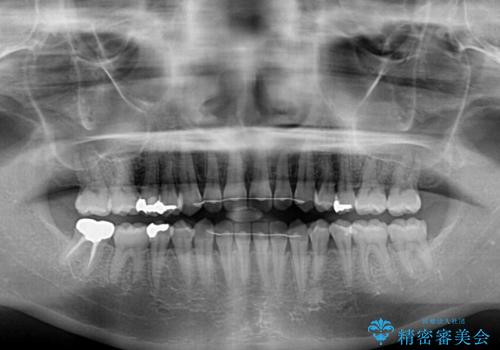

- 上の前歯の隙間を気にして来院された患者様です。

インビザラインの自己管理は自信がないとのことで、ワイヤー矯正により隙間を閉じていくこととしました。

下の前歯が上の前歯を突き上げるように咬合するため、咬み合わせの位置を改善しながら隙間を閉じていきました。

元々の歯並びが悪くなかったため、9ヶ月で綺麗に仕上がりました。